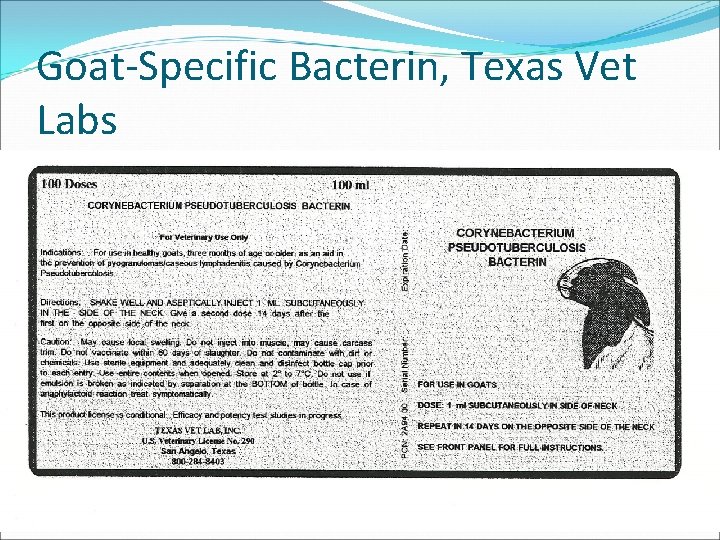

Goat-Specific Bacterin, Texas Vet Labs

Texas Vet Labs Vaccine… �Conditionally licensed �Dependent on state �Approved in Oklahoma �Must check with state vet